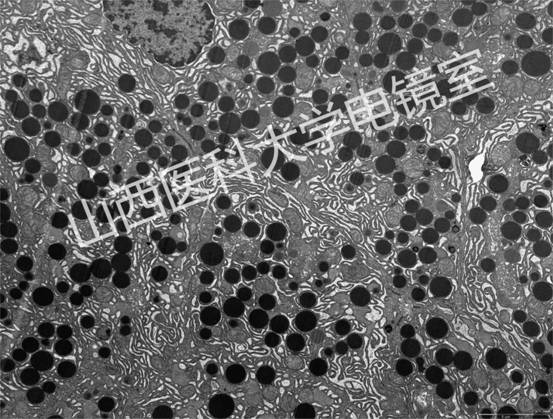

代表性圖譜:

腎